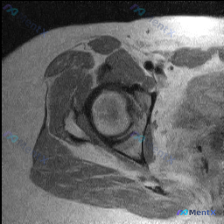

单张髋关节MRI T1轴位片分析:未见盂唇病变,但这几个关键点值得留意

最近整理到一个髋关节MRI影像分析的病例,患者临床怀疑盂唇病变,但提供的单张T1轴位片未显示明确异常。报告详细分析了解剖结构、病变可能性、诊断路径等内容,其中有几个点比较值得讨论:

- 单张T1轴位片对盂唇病变的敏感性如何?

- 影像阴性但临床高度怀疑时,下一步应如何评估?

- 盂唇病变的诊断有哪些常见陷阱?